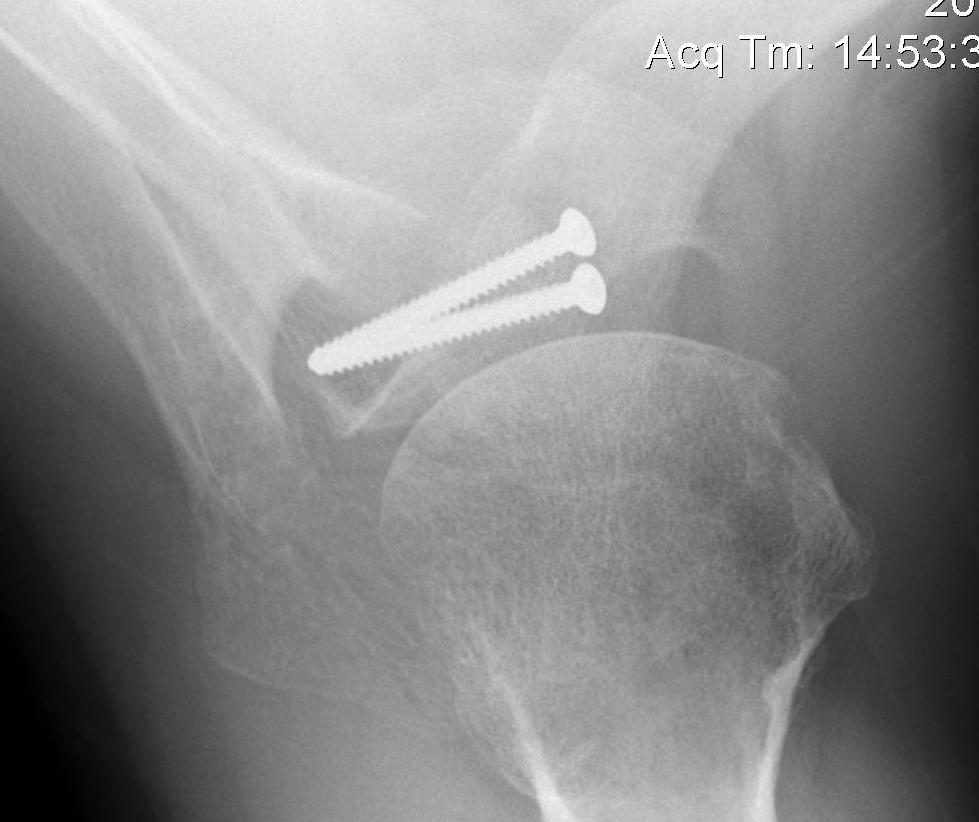

Secure coracoid

- inferior half of glenoid

- no medial overhang

- secure with 2 x bicortical screws with compression

Hardware issues

Screw backout

Intra-articular screw

Graft malposition

Screws and graft too medial